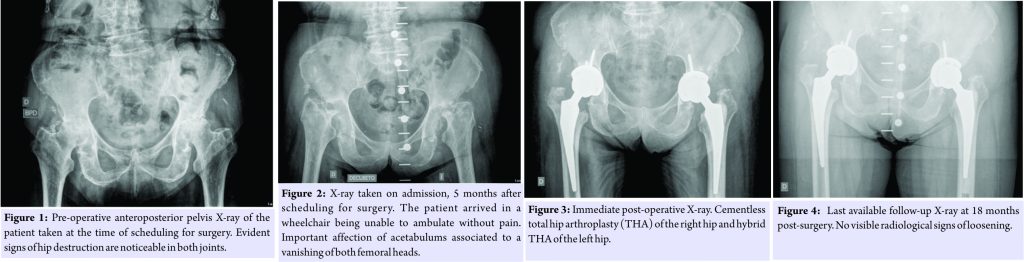

A 84-year-old female was scheduled for bilateral total hip replacement due to osteoarthritis of both hips (Fig. 1). Medical history included chronic Hepatitis C virus infection with no other medical conditions reported. The patient was allowed to decide which hip would be performed first. 5 months after scheduling, the patient was admitted for surgery arriving in a wheelchair, and new pelvis radiographs were taken (Fig. 2). Other causes of the rapid destruction of the hip joint were ruled out, and the patient was diagnosed of bilateral RDO.

Keeping in mind a possible septic etiology, despite there was no history of septicemia and inflammatory markers were elevated due to chronic hepatitis, we decided to take samples for microbiology and histology during the procedures. The right hip was performed through an anterior approach by a senior surgeon following standard antibiotic prophylaxis with 2 g of cefazolin 20 min before skin incision. An uncemented prosthesis was implanted with no complications. Femoral head destruction led to an important defect in the posterior and superior wall of the acetabulum. This conditioned high and medial implantation of the cup to achieve stability. 4 days after the first procedure was performed, one out of six cultures was positive for Enterococcus faecium with no local and systemic signs of infection or pain. Synovial biopsy revealed fibrosis, chronic inflammation, calcifications, macrophages, and osteoclast giant cells with no signs of acute inflammation. Urine cultures were negative. The Musculoskeletal Infection Society criteria [3] were not met and the patient did not receive antibiotic treatment. 6 days later, after a favorable post-operative evolution, the left hip was performed through a posterior approach by a different senior surgeon with the same hip system but with a cemented stem (Fig. 3). In the left hip, the acetabulum was also affected by the bone destruction, but the cup was able to be placed at a correct height. This ended up with a leg length discrepancy that is well tolerated by the patient taking into account her previous functional status. 5 days after the second procedure and following a post-operative period without complications, the patient was discharged before obtaining definitive microbiological results. Cement was loaded with gentamycin, and the same antibiotic prophylaxis protocol was used. For the second surgery, three out of four samples were positive for the same microorganism. 2 weeks later, the patient was readmitted due to wound drainage of the right hip. Surgical debridement and irrigation with the exchange of the modular components were performed. Empiric antibiotic treatment was started with teicoplanin, amikacin, and rifampicin according to the Infectious Diseases Department’s protocol at our institution. Amikacin was stopped 3 days after surgery because no Gram-negative Bacilli were isolated. All four samples obtained during the debridement were positive for E. faecium 5 days after surgery with identical sensitivity tests as for the first hip. Pathogen-specific antibiotic treatment was then started with amoxicillin and rifampicin. 2 weeks after debridement and 1 month after the first surgery, the patient was again readmitted due to wound drainage of the same right hip. Again, surgical debridement and exchange of modular components were performed continuing with the same antibiotic treatment. For the second debridement, one out of five samples was positive for Propionibacterium acnes. Amoxicilin treatment was followed during 3 months. At 18 months after surgery, the patient had recovered to previous full activity. Blood tests at 18 months showed normal C-reactive protein levels and an erythrocyte sedimentation rate of 40 mm/h. In the last X-ray control, there were no signs of loosening (Fig. 4). Patient regained complete gait independence without pain. No further complications were reported.